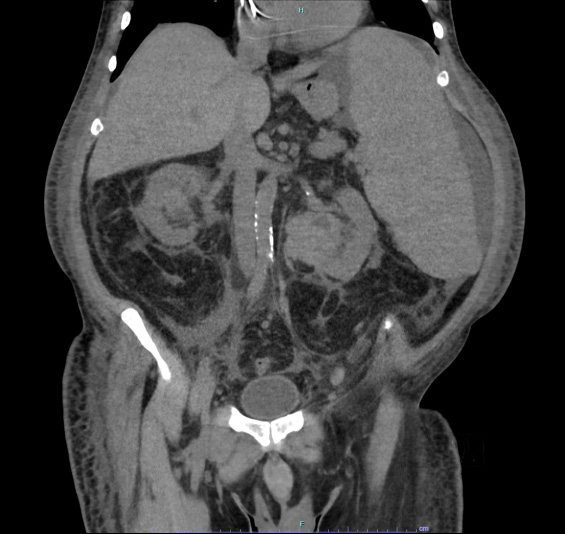

Figure 1. Abdominal computed tomography showing bilateral kidney solid lesions (more evident at the left kidney) together with the known splenomegaly.

In February 2018, the patient went into emergency department and was admitted to hospital because of persistent fever and worsening of renal function. Laboratory test showed a moderate normocytic anemia with increased inflammatory indexes and normal white blood cells (WBC) and platelet count (Table I). Blood cultures and Legionella and Pneumococcus urinary antigens were negative, while a chest X-ray revealed a left parenchymal thickening associated to pleural effusion. Broad spectrum antibiotic therapy with ceftriaxone and levofloxacine was started. Because of the worsening of renal function, an abdomen ultrasound (US) was performed and revealed left ureteronephrosis with presence of a suspected mass at the pyeloureteral joint. A concomitant splenomegaly was recorded with a spleen diameter of 22 cm. The CT scan confirmed a hyperdense lesion which wrapped the left caliceal cavities (Figure 1).

A similar finding, though less evident, was described at the right kidney. Imaging studies were repeated at the end of antibiotic therapy after resolution of fever and normalization of C-reactive protein values, but the lesion appeared unmodified. In the following days, a rapid increase of LDH and the onset of leucocytosis with a 2% of CD33+ CD34- CD117+ HLA-DR+ blasts in peripheral blood smear was observed. Therefore, a bone marrow evaluation and a US-guided needle biopsy of the left renal mass were performed. Both the histology profiles were consistent with acute monocytic leukemia (Figure 2).